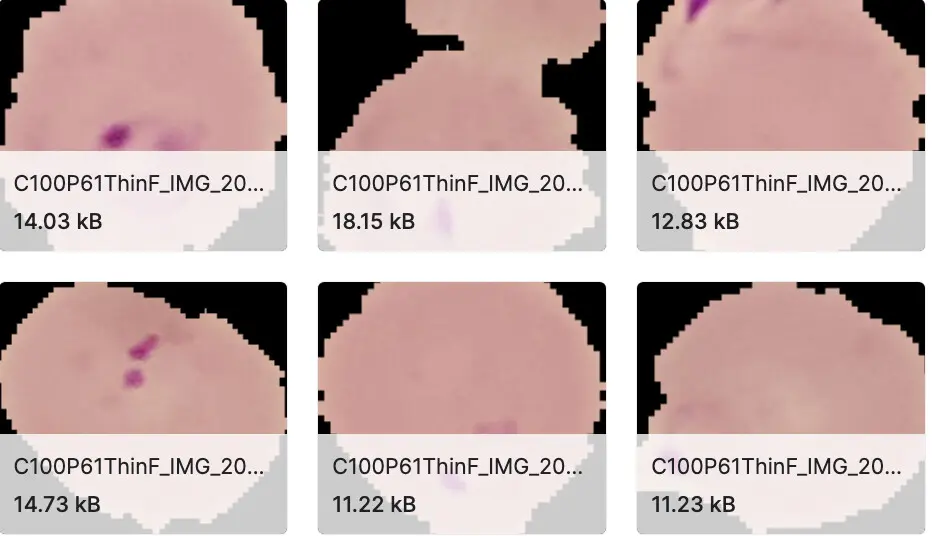

细胞实例分割数据集

数据集下载链接:http://ewz6s.avtk.cn/25

引入了新的大型细胞实例分割数据集 (CISD)。它包括3911个样品,其中包含至少两个接触或重叠的尿路上皮细胞。细胞实例由训练有素的细胞技术人员手动注释。所有样品均从 30 张数字细胞学载玻片中提取,这些载玻片用 9 种不同的 Papanicolaou 染色染色。细胞学载玻片使用豪洛捷 ThinPrep®5000 处理器从健康患者的尿液样本中制备,并常规使用安捷伦 Dako 盖染色仪®进行染色。最终使用具有21个焦平面的Hamamatsu NanoZoomer®S360对载玻片进行数字化,并以扫描仪自动对焦确定的最佳焦平面为中心。